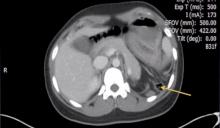

This video demonstrates a laparoscopic repair of symptomatic left-side Bochdalek hernia in a 20-year-old female. The patient presented with chronic intermittent constipation, nausea, and emesis. A CT scan revealed the hernial defect.